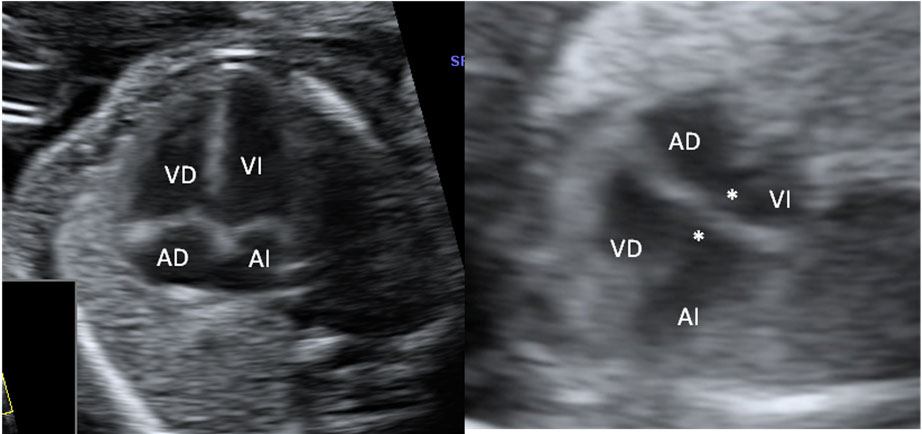

En la ecografía en 2D de la semana 20 de embarazo se hace un estudio pormenorizado de los órganos internos del feto y de su anatomía. Así se descubren muchas malformaciones congénitas, como en este caso, un pie equinovaro o zambo.

Imagen ecográfica de pie zambo o equinovaro